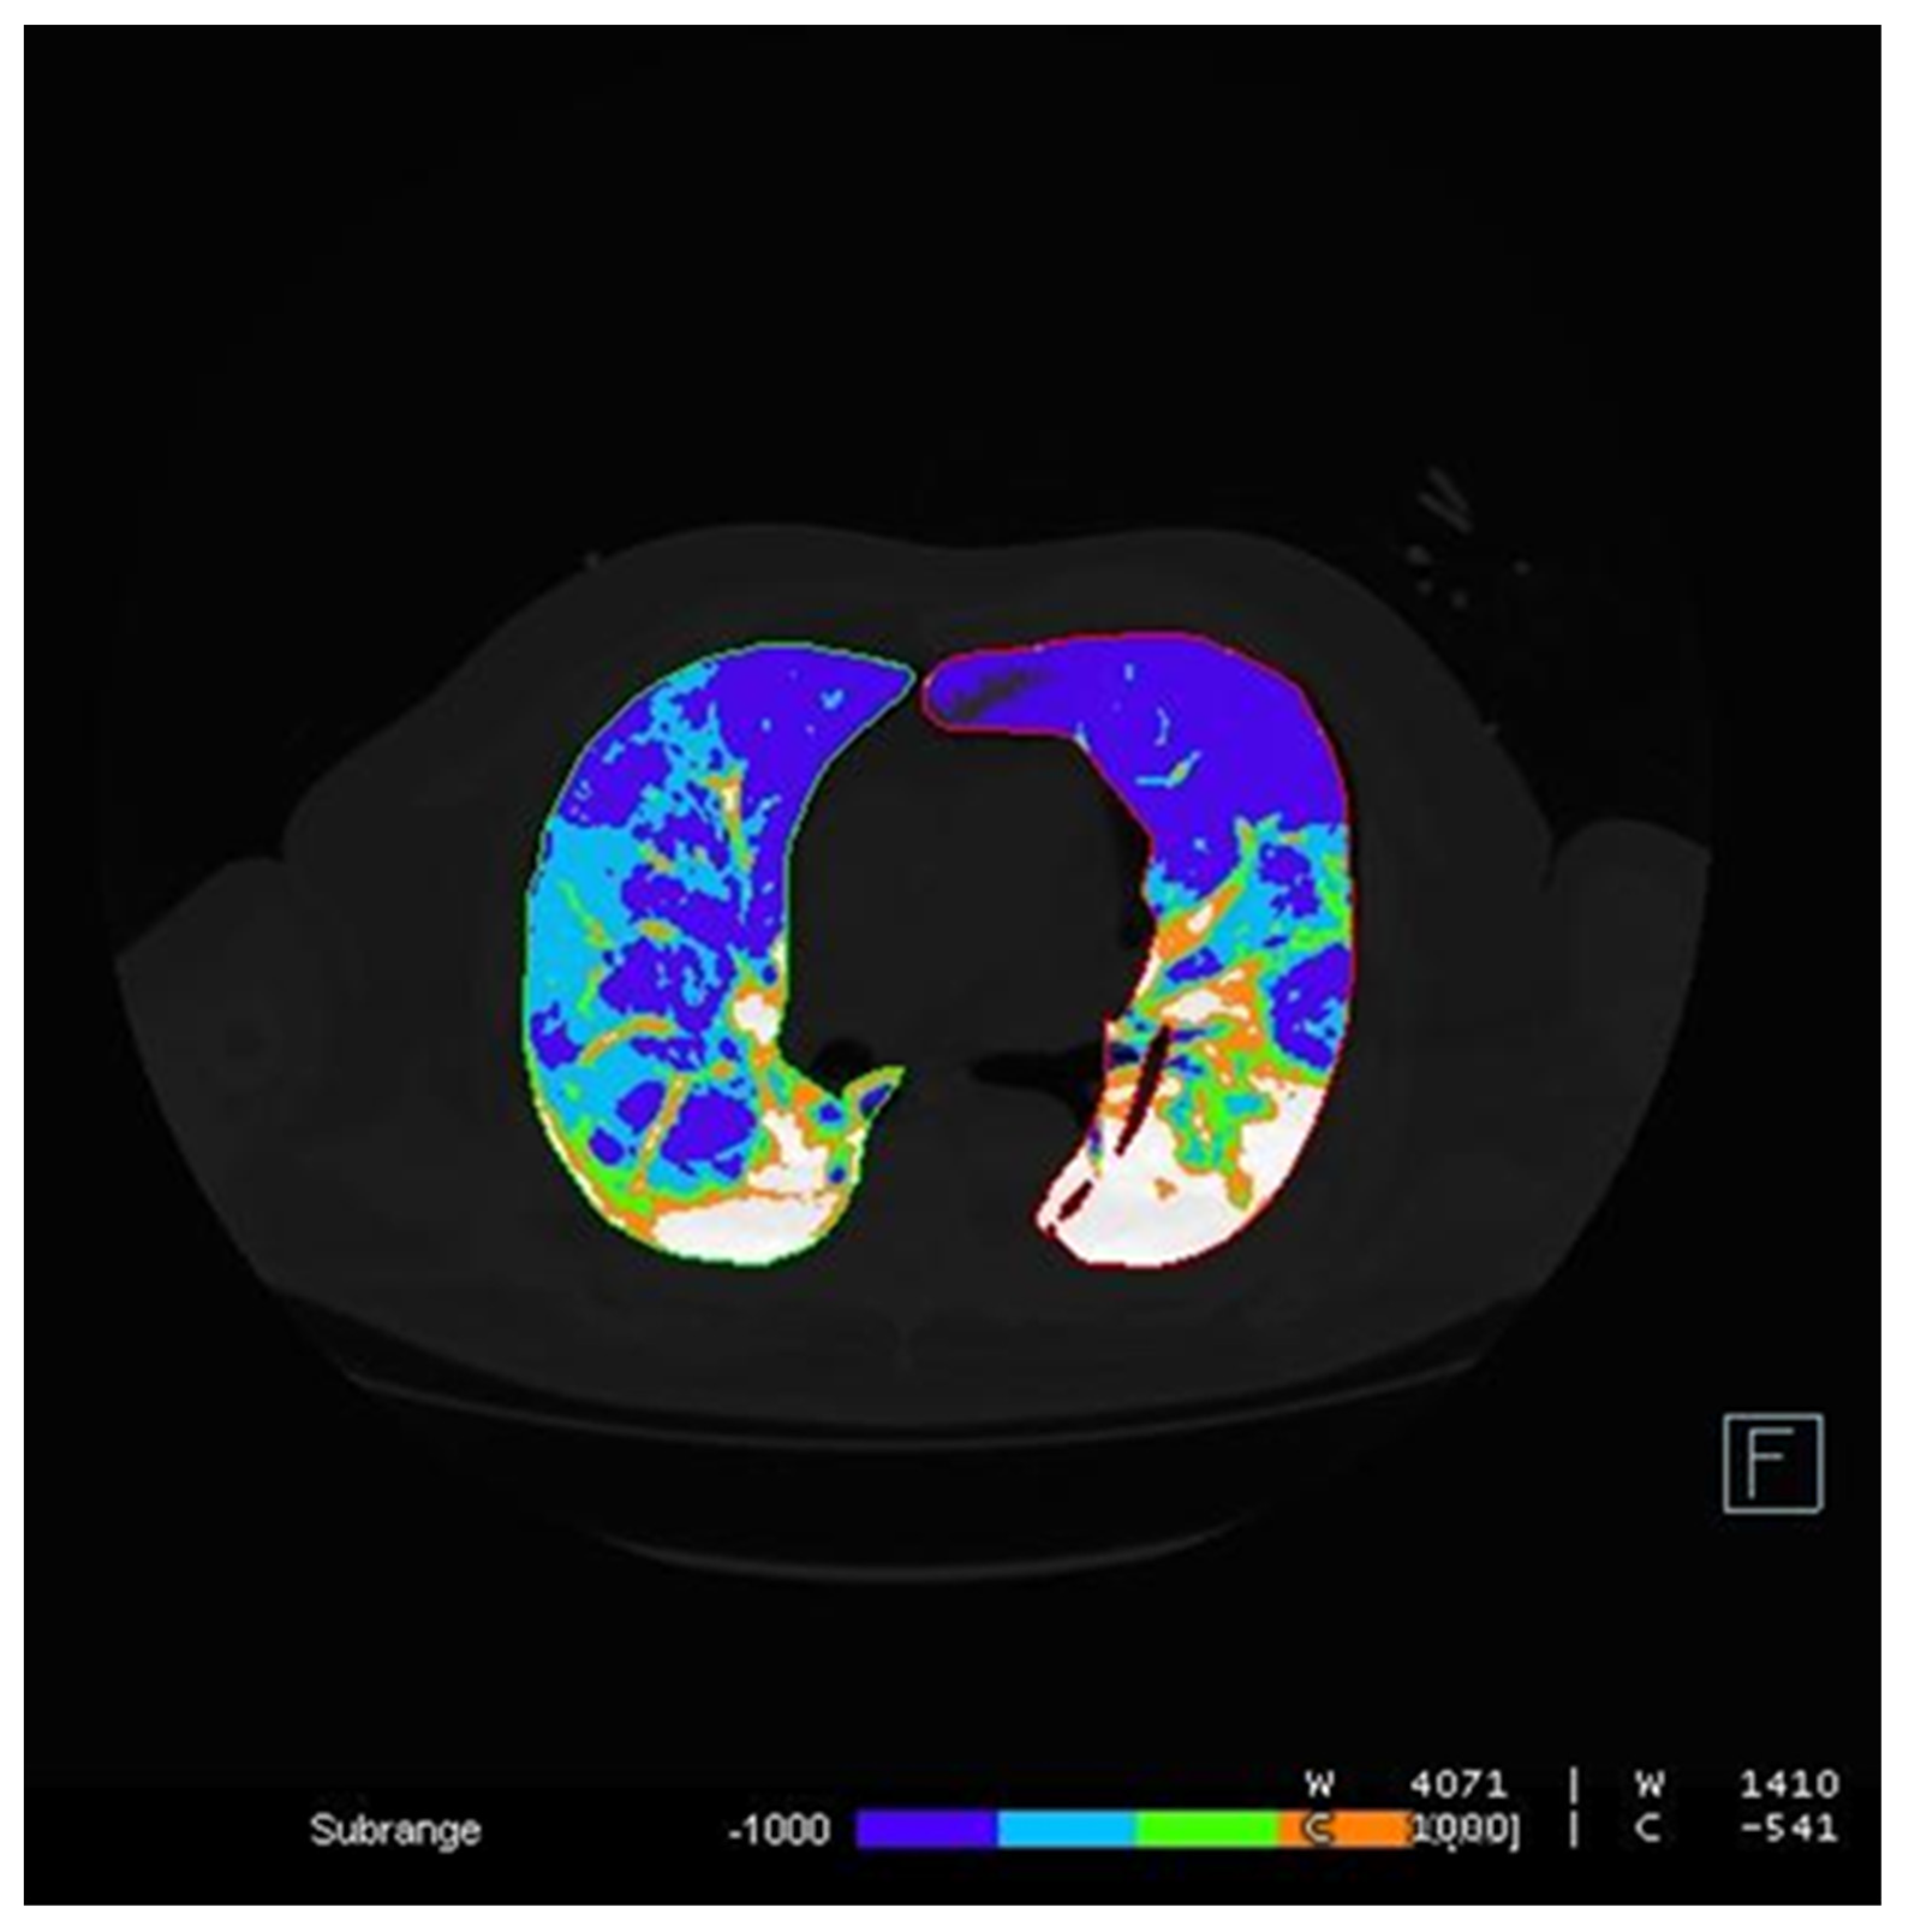

2.3. Image Analysis

- -